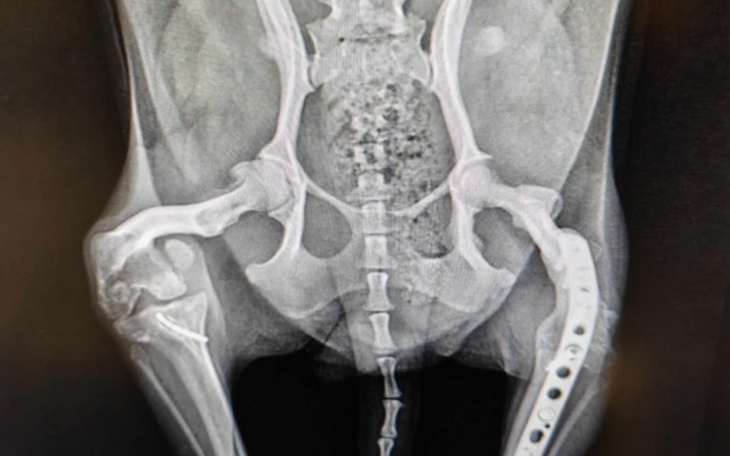

Fela jest po operacjach obu nóżek😢. W jednej wykonano usztywnienie stawu (artrodeza lewego stawu), bo tylko to można było zrobić, była tak wykręcona, do czego doprowadziła poprzednia "właścicielka". Druga nóżka miała reperowaną rzepkę, niestety okazało się, że wada się pogłebiła. Była wielka nadzieja na szczęśliwy koniec kłopotów ortopedycznych.

Niestety potrzeba reoperacji, która niestety nie da gwarancji poprawy, ale choć lepsze samopoczucie. W przeciwnym razie zostanie też usztywniona jak lewa, co mam nadzieję, okaże się śródoperacyjnie. Obecnie tylko tej drugiej usztywnionej używa.

Koszt pierwszej operacji to 5 tys, drugiej 3 tys. plus badania. Teraz będzie 5-6 tys. plus tomografia. Masakra.